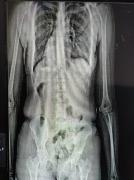

Ao passar pelo equipamento, policiais penais identificaram irregularidades na imagem corporal da visitante, companheira de um interno da unidade. As imagens apontaram a presença de um objeto em formato cilíndrico introduzido na cavidade pélvica.

Ainda na manhã de terça-feira (6), no Conjunto Penal de Barreiras, uma outra mulher foi detida ao tentar burlar o sistema de segurança ao esconder drogas nas partes íntimas para ingressar na unidade. A tentativa, no entanto, foi frustrada pelos agentes com o auxílio da mesma tecnologia de escaneamento corporal.